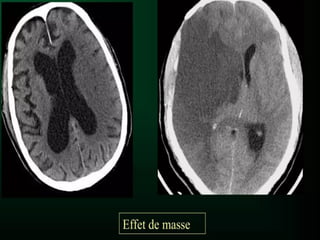

• Effet de masse : refoulement voire effacement

des sillons et/ou des ventricules en regard

d’une lésion

EFFET DE MASSE

• Déviation de la ligne médiane : perte de

l'alignement dans l'axe de la faux du cerveau

secondaire a un effet de masse ( signe un

engagement sous-falcoriel )